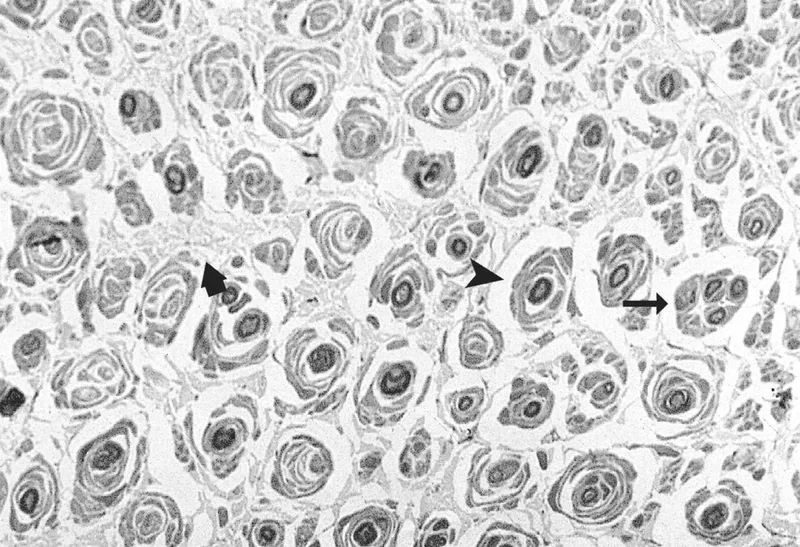

- Morphology: "Onion bulb" formations (repetitive demyelination & remyelination).

⭐ CMT1A, due to PMP22 gene duplication, is the most common inherited neuropathy, characterized by hypertrophic "onion bulb" Schwann cell changes visible on biopsy.